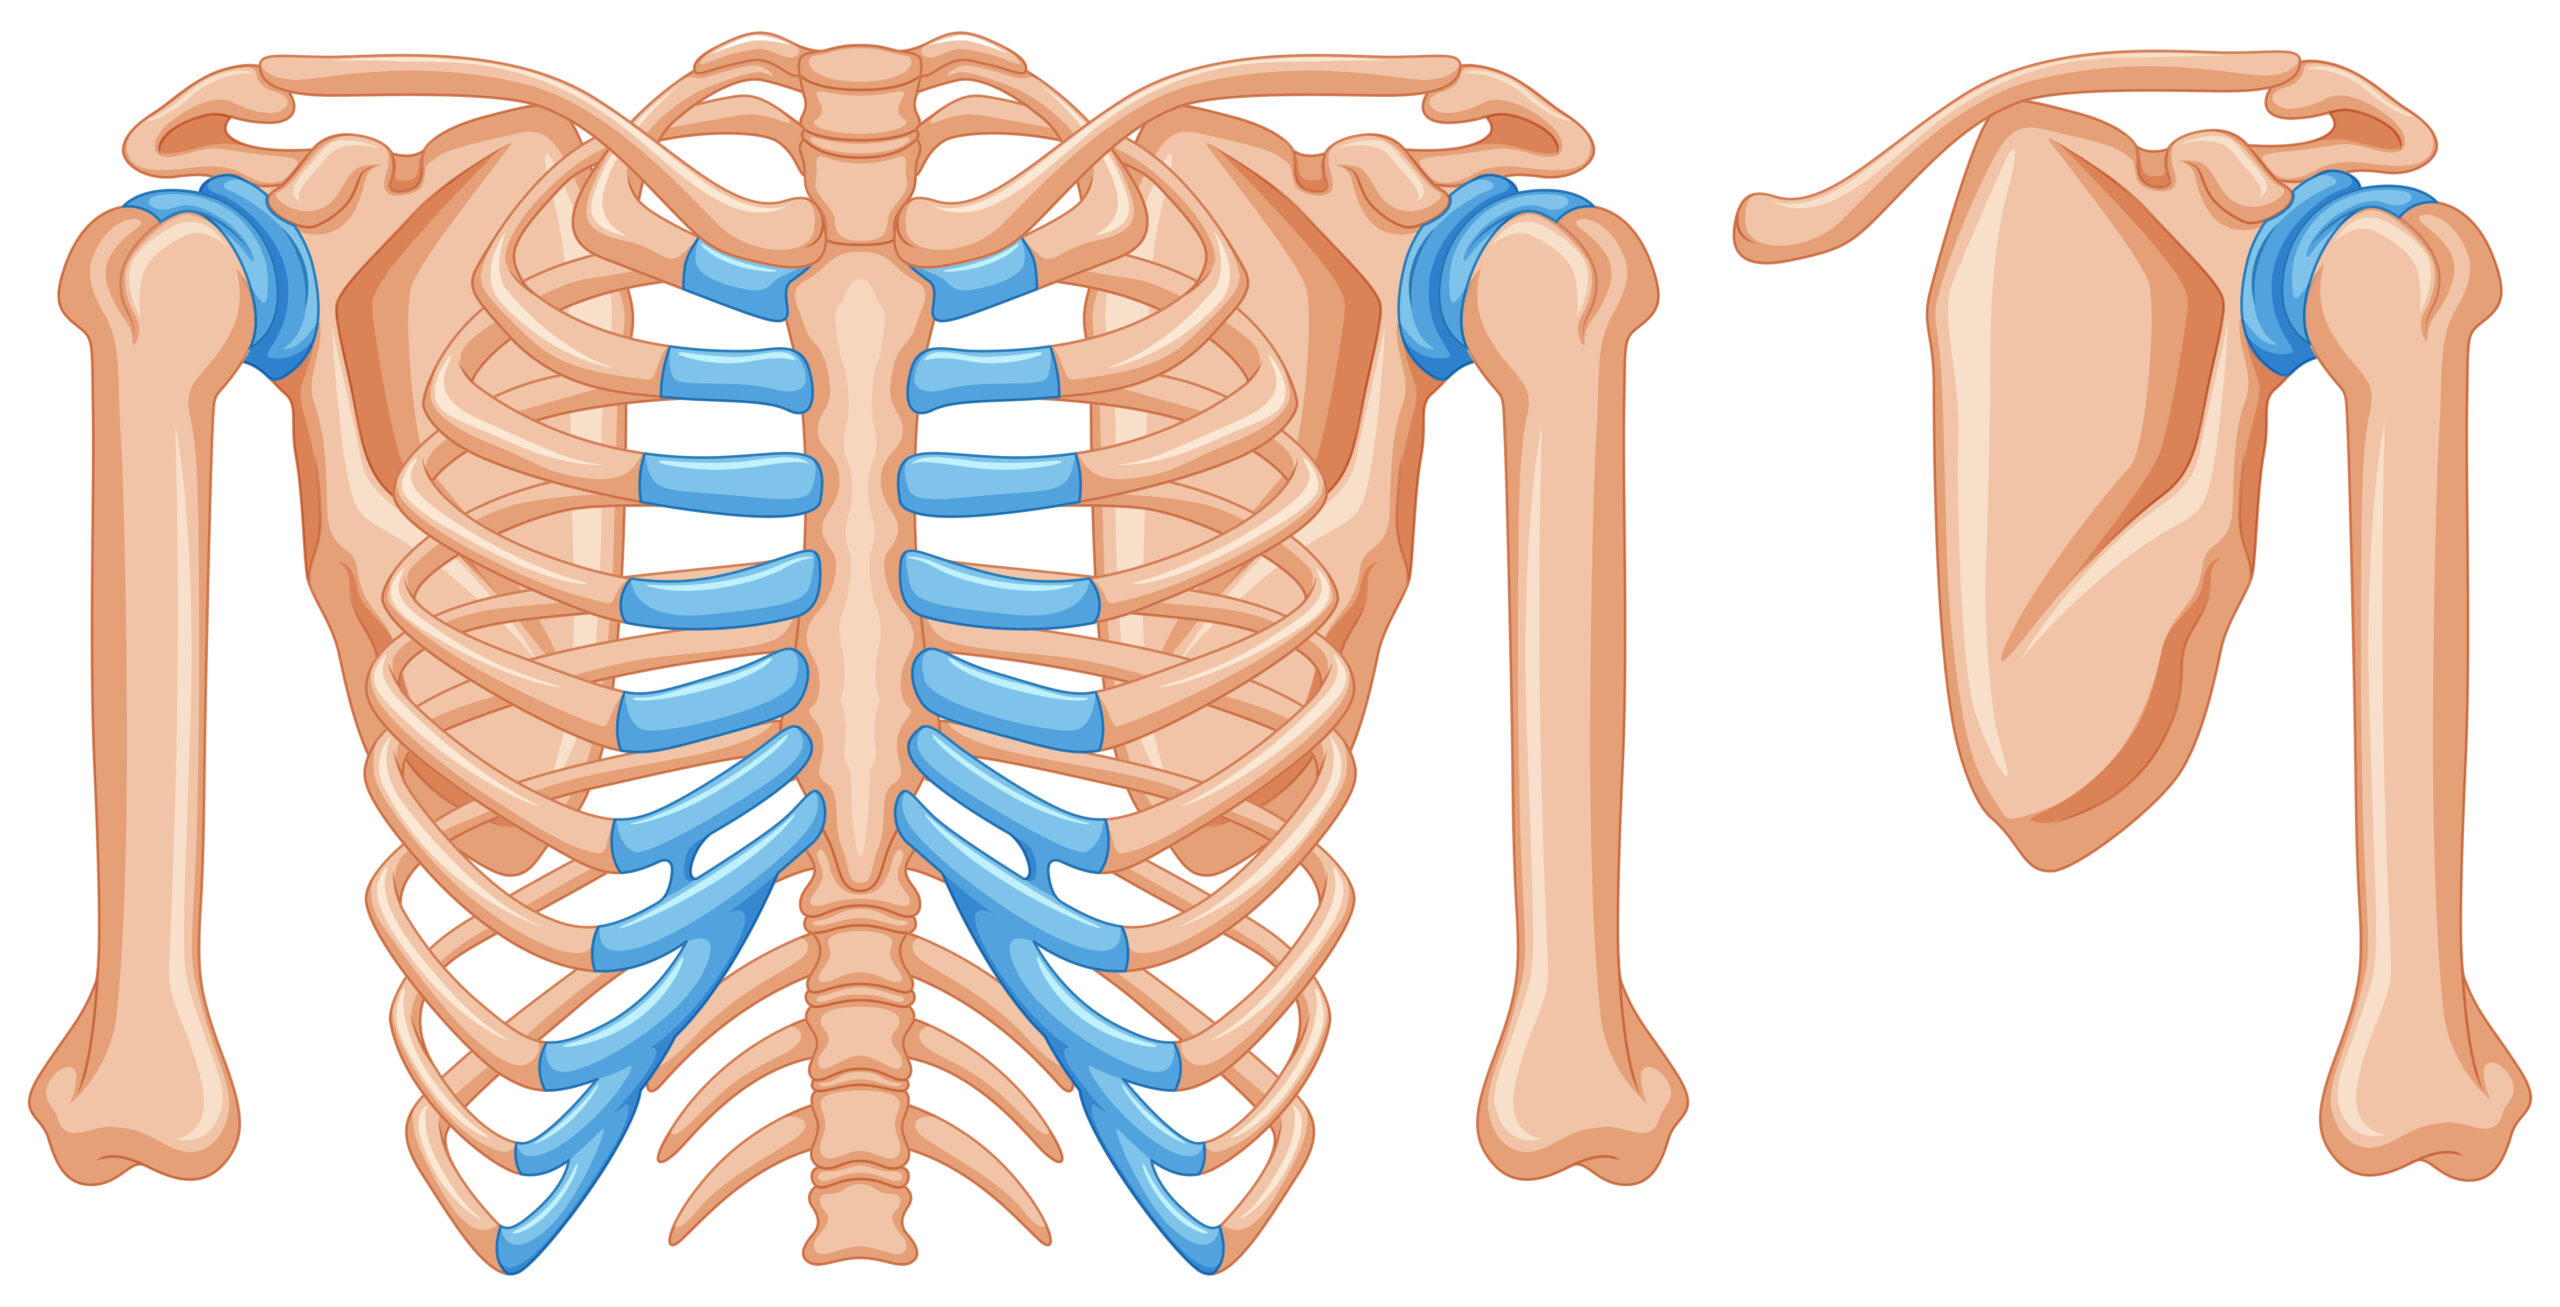

まず胸郭とは、肋骨・胸椎・胸骨で構成される上半身の骨格のことを指します。胸郭は本来、呼吸に合わせて広がったり閉じたりしながら、体幹の動きにも関わっています。

また、背骨の中でも胸椎(胸の背骨)は回旋(ひねり)や伸展(反る動き)を担う重要な部分です。

しかし、デスクワークやスマホの使用、猫背姿勢が続くと胸郭周りの筋肉が硬くなり、肋骨や胸椎の動きが悪くなります。すると本来胸郭が担うべき動きが失われ、体を反らす・ひねるといった動作を腰が代わりに行うようになります。

腰椎(腰の背骨)は、実は構造的に大きくひねる動きが得意ではありません。

それにもかかわらず、胸郭が動かないことで腰が無理に動くと、椎間関節や周囲の筋肉に負担がかかりやすくなります。これが慢性的な腰痛につながる原因の一つです。